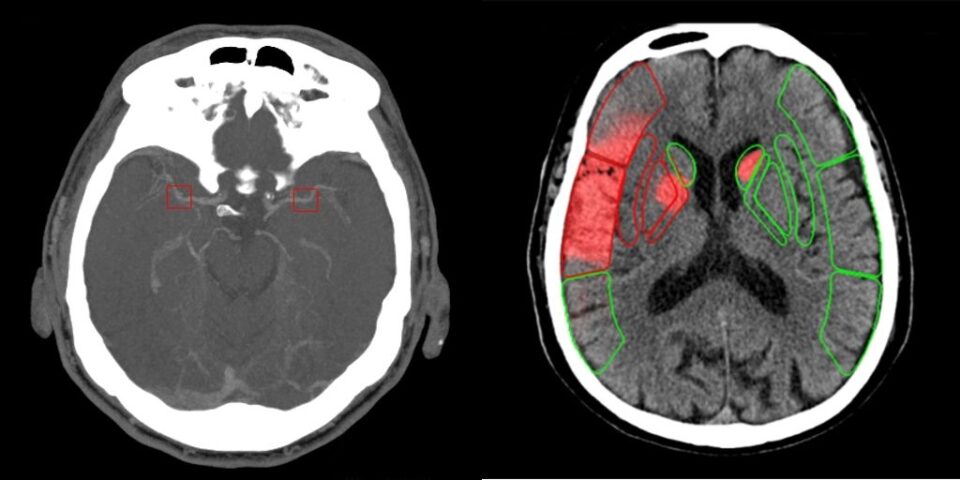

شركة AI-Stroke الناشئة الفرنسية المتخصصة في تكنولوجيا الصحة (MedTech) قامت مؤخرًا بجمع 4.6 مليون دولار لتطوير أداة تقييم سريعة للسكتات الدماغية قبل التصوير المقطعي. يهدف هذا التمويل، الذي قادته شركة Heka التابعة لـ Newfund VC بدعم من مستثمرين بارزين، إلى تسهيل المسار التنظيمي للشركة مع إدارة الغذاء والدواء الأمريكية (FDA) وإطلاق دراسات سريرية متعددة المواقع في مراكز السكتات الدماغية الرائدة في الولايات المتحدة. تأسست AI-Stroke في عام 2022، وهي تحول الهواتف الذكية والأجهزة اللوحية إلى أدوات تقييم سريع للسكتات الدماغية، مما يمكّن المسعفين والممرضين من اكتشاف علامات السكتة الدماغية في غضون ثوانٍ من خلال تحليل الفيديو. يعتمد النظام على مجموعة واسعة من البيانات السريرية، ويكتشف ضعف عدد حالات السكتة الدماغية الحقيقية. كما رحبت الشركة بأربعة خبراء بارزين في لجنتها الاستشارية الطبية لتعزيز مهمتها في تزويد خدمات الطوارئ بدعم عصبي مدعوم بالذكاء الاصطناعي. تستعد AI-Stroke للتوسع في السوق الأمريكية وإرساء معيار جديد للرعاية في مجال اكتشاف السكتات الدماغية.